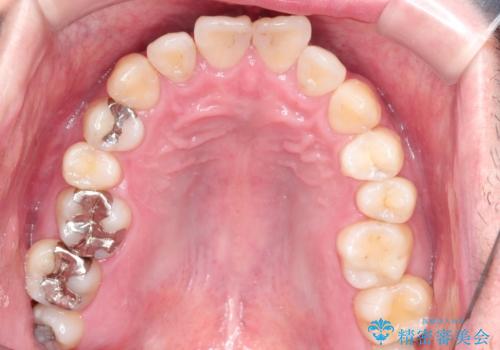

全体的ながたつきをインビザラインで改善

- 全体的ながたつきを主訴に来院されました。

歯と歯の間をわずかに削って、スペースをつくり並べる計画としました。

しっかりと、マウスピースの装着時間を守っていただいたので、スムーズに治療をおえることができました。